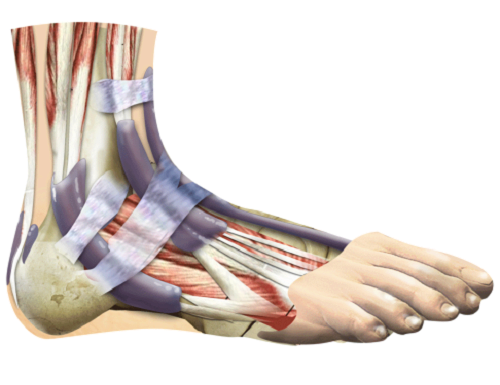

Синовіальна сумка (бурса) являє собою порожнинне освіту з синовіальної мембрани і синовіальної рідини. Ця порожнина розташовується в зонах тертя сухожиль або суглобових поверхонь, і її мета полягає в забезпеченні більш комфортних умов для їх роботи і запобігання травм.

1. ахіллобурсіт, або п'ятковий бурсит - запалення синовіальної сумки, навколишнього аххілови сухожилля. Може бути переднім і заднім. При передньому ахіллобурсіт запалюється сумка перед місцем, де кріпиться ахіллове сухожилля до кістки п'яти, а при задньому - сумка між сухожиллям і шкірою.

2. Бурсит великого пальця ноги. Причиною виникнення може стати деформація суглоба великого пальця, в результаті чого його кісточка почне випирати назовні. Це призведе до тертя кісточки об поверхню взуття і викличе запалення суглобової сумки.

3. подпяточная бурсит, причиною прояви якого служить дистрофічний процес, що супроводжується запаленням подпяточная області стопи. В результаті захворювання утворюється шпора п'яткової кістки.

П'яткова шпора є хронічним захворюванням, що супроводжується утворенням клювовидного наросту на поверхні підошви в області п'яткової кістки, периоститом і запаленням синовіальної сумки пяточногоапоневроза.